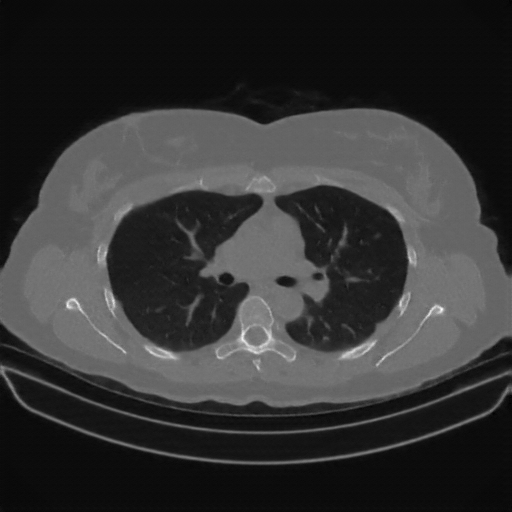

Slice 70 Targeting Evaluation

Slice: Slice_70

Slice Thickness: 1.5mm

Conversion: NATIVE β†’ VENOUS

Targeted Slice 70 - Lung Window Analysis (Generated vs Real Venous)

0.763

Lung SSIM

85.0

Lung RMSE

36.7

Lung MAE

Average Lung Window Metrics Across All Slices (170 slices) - Generated vs Real Venous

0.767

Lung SSIM (Avg)

89.5

Lung RMSE (Avg)

37.4

Lung MAE (Avg)

Original NATIVE CT scan (input)

No window - Raw intensity values

Lung window (WL -600, WW 1500 β†’ Low βˆ’1350, High +150)